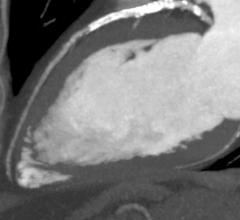

August 14, 2014 — Toshiba Medical Systems Europe will introduce the SURE Subtraction Coronary software at the 2014…

Sponsored Content